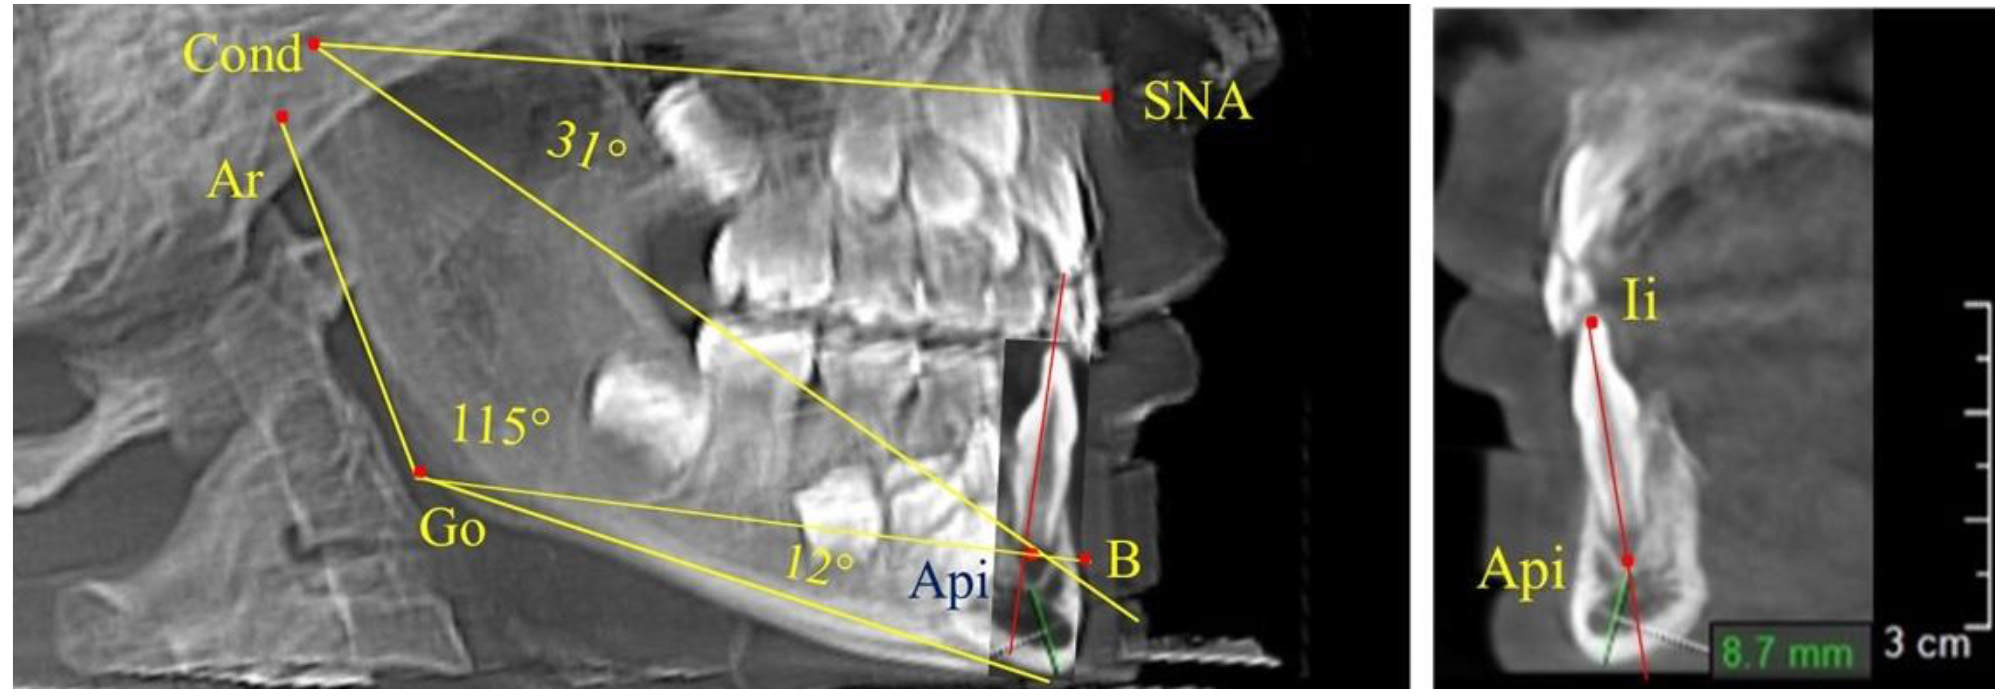

После смены всех молочных зубов (анализ 9 ТРГ) и после прорезывания вторых постоянных моляров (7 человек) происходил очередной этап подъема высоты прикуса с увеличением размеров костей гнатической части лица. Однако величина основного угла гнатической части лица SNA-Cond-Api, так же как в молочном и сменном прикусе, в норме составляла (30,02 ± 1,25)°, что не имело достоверных различий (р ˃ 0,05) с аналогичным параметром, анализируемом в других группах исследования. Угол нижней челюсти и его составляющие отличались вариабельностью параметров при различных показателях нижнечелюстного угла (рис. 6).

Рис. 6. Варианты 3D рентгенограмм детей после смены всех молочных зубов (а) и после прорезывания вторых моляров (б)

Таким образом, данные, полученные при исследовании детей с физиологическим прикусом в различные периоды онтогенеза, показали, что величина основного угла гнатической части лица SNA-Cond-Api была относительно стабильным параметром, вне зависимости от линейных параметров челюстных костей. Данный показатель может служить ориентиром для дифференциальной диагностики зубоальвеолярных и гнатических форм аномалий окклюзии в вертикальном направлении.

Особенность анализа телерентгенограммы в периоде сменного прикуса заключалась в том, что наслоение зачатков постоянных зубов затрудняло определение апикальной точки нижнего резца. В подобных случаях использовали метод совмещенного анализа телерентгенограммы с фрагментом томограммы, на котором, также как и на телерентгенограмме, определяли положение резцовой и апикальной точек с построением условной вертикали, которая служила ориентиром для совмещения фрагментов (рис. 2).

Рис. 2. Особенности совмещения телерентгенограммы с фрагментом томограммы в сменном прикусе